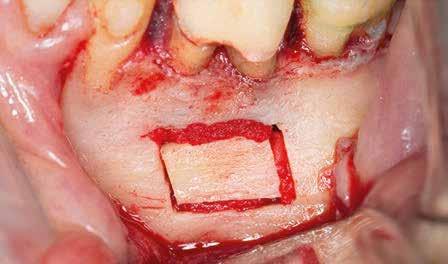

1. a-n. ábrák: Preoperatív CBCT-felvétel a bal alsó 6-os (3.6) fogról. Az axialis (a), coronalis (b) és sagittalis (c) nézeteken a mezialis és distalis gyökerek apicalis harmada körül sugáráteresztő zóna és ép buccalis corticalis csont látható. Egy olyan sablont terveztünk, amely jelezte a csontablak határait az apicalis terület pontos elérése érdekében (d). A mikrosebészeti bevatkozás során a sablont a helyére illesztettük (e), a csontablak határait megjelöltük (f) egy Piezotome CUBE LED kézi-darabba fogott fűrésszel, majd kivágtuk és eltávolítottuk (g és h) az apicalis területhez történő hozzáférés, illetve a mezialis és distalis gyökerek rezekciójának, retrográd preparációjának és retrográd gyökértömésének elvégzése érdekében (i). Végezetül a csontablakot visszaillesztettük és kollagén szivaccsal stabilizáltuk (j). A műtét után közvetlenül készített röntgenfelvétel a 3.6-os fogról (k). A kétéves kontroll során készített CBCT-felvétel: axialis (l), coronalis (m) és sagittalis (n) nézetek.

Klinikai vizsgálat során vertikális kopogtatási érzékenységet jelzett. A fog körül mérhető szondázási mélység és a fogmobilitás fiziológiás volt. A CBCT-felvételen nem észleltünk a csontos regeneráció megindulására utaló jeleket (1. a–c. ábrák). A korábban gyökérkezelt, gyökértömött és revideált 3.6-os fog esetében az alábbi diagnózis került felállításra: periodontitis periapicalis symptomatica. A panaszokat okozó fog további ellátása során navigált endodonciai mikrosebészetet kívántunk alkalmazni. Az alsó állcsontról intraorális szkent (TRIOS, 3Shape) készítettünk, és a felszíni topográfiát tartalmazó STL fájlt, valamint a CBCT-felvétel készítése során nyert DICOM fájlokat a Blue Sky Bio szoftver segítségével egyesítettük. A sebészi sablon megtervezésére az így kapott háromdimenziós képet használtuk. A sablon kialakítása során arra törekedtünk, hogy a sablon egyértelműen meghatározza a gyökércsúcsi terület eléréséhez szükséges csontablak határait (1. d. ábra)

A beavatkozás során helyi érzéstelenítésben teljes vastagságú mucoperiostealis lebenyt képeztünk, és a sablon segítségével bejelöltük a preparálandó csontablak határait. Az ablak széleinek megfelelően Piezotome CUBE LED kézi-darabbal (ACTEON) a kortikális teljes vastagságában vágást ejtettünk, majd az így kapott csontlemezt (ablakot) eltávolítottuk (1. e–h. ábra), és ezt követően steril fiziológiás sóoldatba helyeztük. A rezekció elvégzését követően (1. i. ábra) a mezialis csatornákat ultrahangos eszközök segítségével (NSK) retrográd irányból preparáltuk, majd az így kialakított mélyedésbe retrográd gyökértömést készítettünk. A tömés anyagául az EndoSequence BC RRM Fast Set Putty-t (Brasseler) választottuk. A tömés elkészítését követően a csontablakot visszaillesztettük, és a stabilizálása érdekében a vágásoknak megfelelően kialakult résekbe kollagén szivacsokat (Collagen Tape, Zimmer Biomet) helyeztünk (1. j-k. ábra). A lebenyt 6/0-s Prolene varratokkal (Corpaul) rögzítettük.

A kétéves kontroll során elvégzett klinikai és radiológiai vizsgálat (CBCT-felvétel) a periapicalis elváltozások megszűnését és a corticalis csontállomány tünet- és szövődménymentes gyógyulását